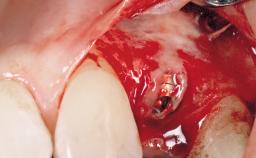

A 42-year-old female patient was referred to our clinic at the School of Dentistry of the University of São Paulo in November 2004, presenting a deficient restoration in the upper left central incisor. The clinical examination revealed no gingival retraction or any signs of gingival inflammation and, therefore, previous periodontal treatment was not considered. The patient presented a high lip line at full smile and a thin tissue biotype. This combination characterized a high-risk situation from an anatomic point of view, which required careful preoperative planning and cautious surgical execution.

Placement Protocol Immediate implant placement

Socket Integrity Sufficient, with intact bone walls

Bone Volume Sufficient, with intact walls

Loading Protocol Immediate